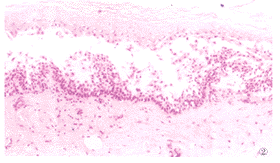

2.PAbIgG亚类诱导表皮棘层松解的组织病理学观察:培养48h后基底层上棘细胞间隙增宽 ,裂隙出现及小疱形成;72h形成明显的棘层松解和表皮内水疱(图2),比较各PAbIgG亚类 所致棘层松解程度无明显差异。正常人IgG作用培养表皮无棘层松解。

图2 天疱疮抗体亚类IgG4作用培养表皮72h的组织病理改变(HE×200)